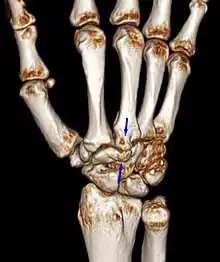

Carpal boss in CT.